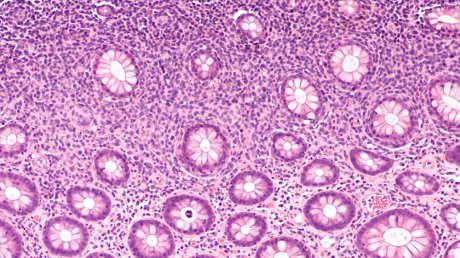

Difuzni B krupnoćelijski limfom Bolest nastaje u B limfocitima, koji počinju da se nekontrolisano dele i rastu Foto: Shutterstock

Bolest nastaje u B limfocitima, koji počinju da se nekontrolisano dele i rastu. Difuzni B krupnoćelijski limfom jedan je od oko 80 tipova limfoma. Pripada grupi agresivnih limfoma sa visokim stepenom proliferacije, razmnožavanja malignih ćelija brzog rasta. Blagovremena terapija i dijagnostika zato su ključni, jer ako se bolest oktrije u ranijem stadijumu rezultati lečenja su bolji.